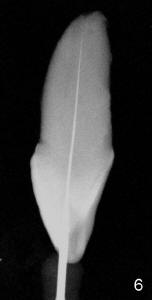

The tooth #8 of a 61-year-old man has obliterated canal probably due to trauma (Fig.1,2 (lateral view)). Initial access shows that the labial portion of the recessed pulpal horn (brown, < in Fig.3 (occlusal view) is not fully exposed, while that the most lingual aspect of the incisal edge (between **) has been removed. Further access appears to be necessary to expose the obliterated pulpal chamber (Fig.7 <) and more of the incisal edge has been violated ( between **). With good exposure, the canal is easily found around the arrowhead (<) in Fig.7. Laterally, the initial file: C6 is straight and slightly labial to the incisal edge (Fig.6). But it is somewhat bent in the front view (Fig.5). After enlargement of the coronal canal with Gates-Glidden files #2 and 3 (Fig.9<), #20 file appears to move distally (<-) and is straighter than the file in Fig.5. Laterally, the #20 file remains without much tension and around the incisal edge (Fig.10). Fig.11 shows occlusal view of the access after application of Gates-Glidden files. Before rotary files, the access is enlarged further both labially and lingually with diamond/carbide endo access burs (Fig.15). Fig.13,14 show 40/.04 file in the canal free without strain. The file seems to move distally further (Fig.13 <-).